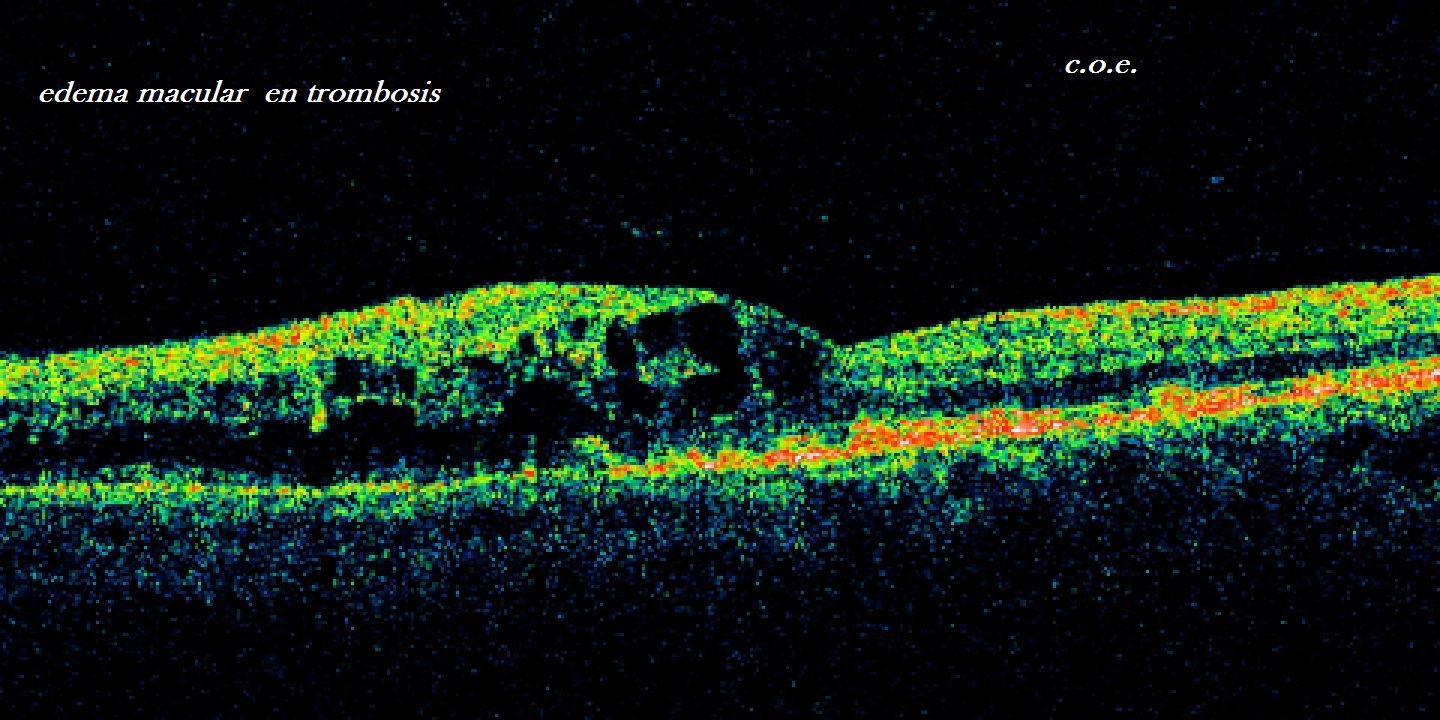

OFTALMOLOGÍA DE VANGUARDIA EN LA COSTA DEL SOL. 35 AÑOS NOS APOYAN, Y AYUDAN A TENER CLARIDAD Y CERTEZA. TOMOGRAFIA RETINA; PIONEROS FACOEMULSIFICACION CATARATA. PIONEROS EN CIRUGÍA REFRACTIVA, Y TRATAMIENTOS PARA LA SEQUEDAD OCULAR . ANTIOXIDANTES EN DMAE.